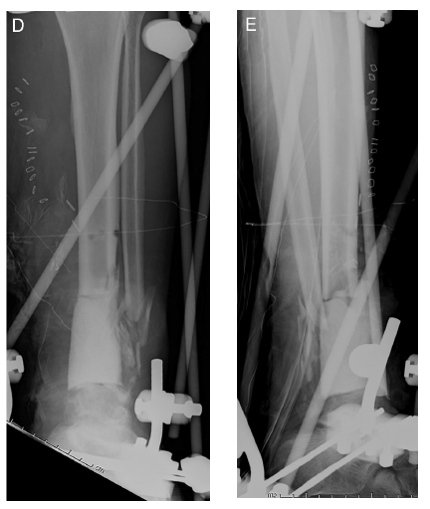

术后复查外支架维持稳定Spacer位置理想力线良好

Stage II取出Spacer   混合材料植骨    仔细缝合软组织覆盖良好

髓内钉内固定踝关节融合